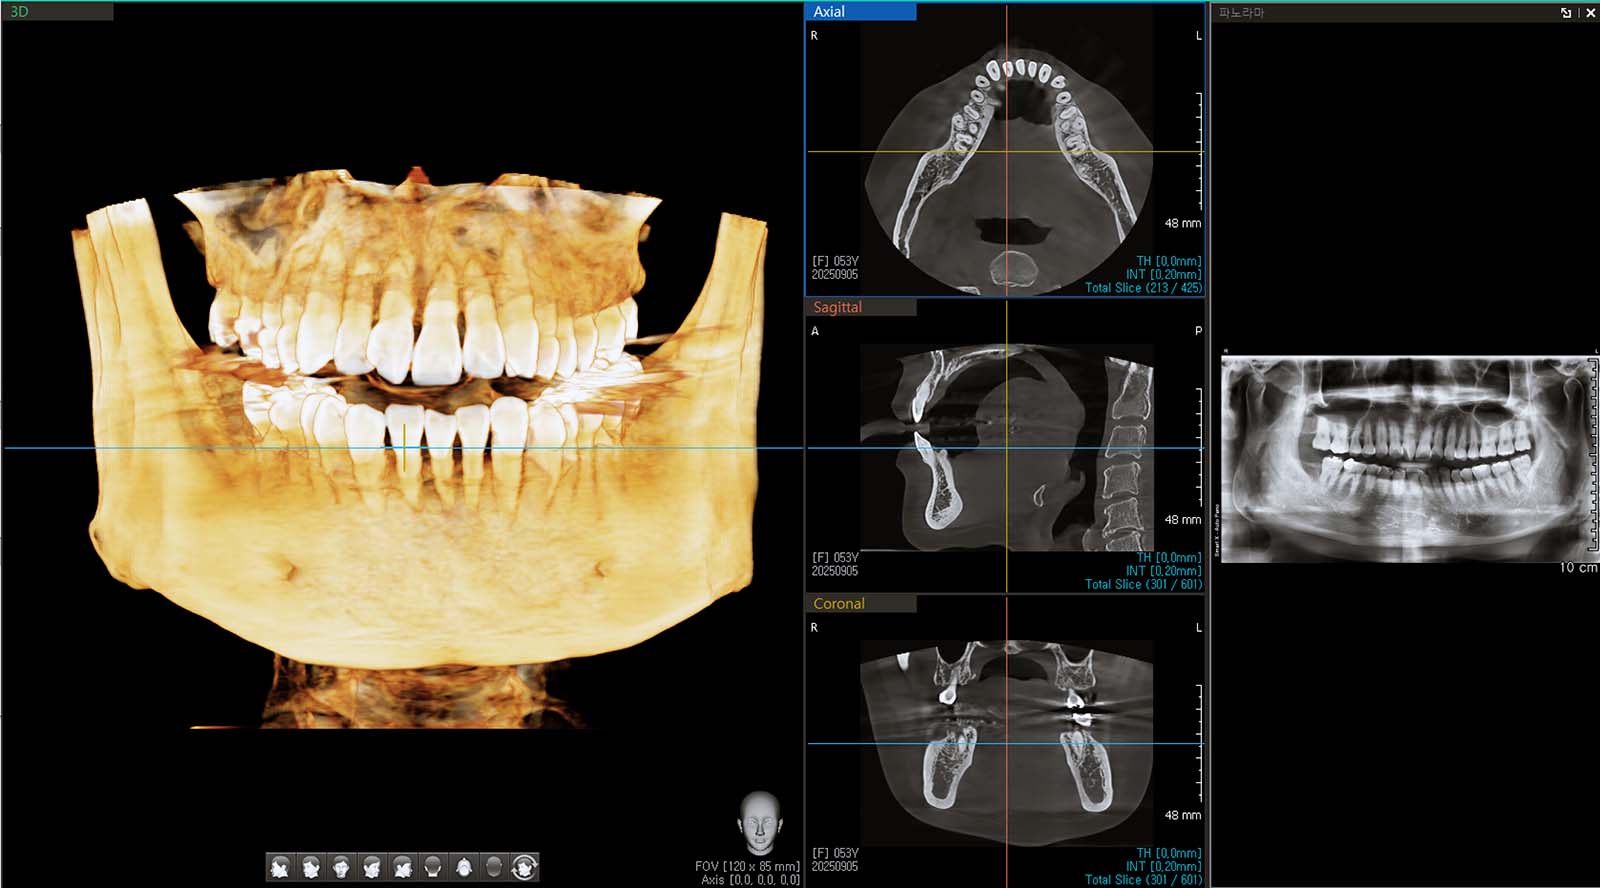

치과 CT 사진. 원하는 위치에서 원하는 각도로 치아를 볼 수 있습니다.

기존 의료용 CT와 달리 원뿔 모양의 X-선 빔을 사용해 구강 및 악안면 부위의 3차원 영상을 촬영합니다. 평면 사진으로 확인하기 어려운 신경관 위치, 매복치 방향, 잇몸뼈 상태 등을 입체적으로 분석할 수 있어 임플란트, 신경 치료, 교정 등 정밀 진단에 필수적입니다. 목동나무치과는 초저선량 기술을 적용해 환자의 방사선 피폭량을 최소화한 바텍(Vatech) 사의 그린 CT를 사용합니다.

사실 CT는 치아를 원하는 위치와 각도에서 3차원으로 확인할 수 있게 해주어 진단의 정확성을 크게 높여주는 축복과도 같은 기술입니다. 단순히 평면으로만 보면 알 수 없었던 문제들을 확인할 수 있습니다. 그린 CT에는 신경 치료 모드가 있어 높은 해상도로 각 치아의 신경 상태를 확인할 수 있습니다.